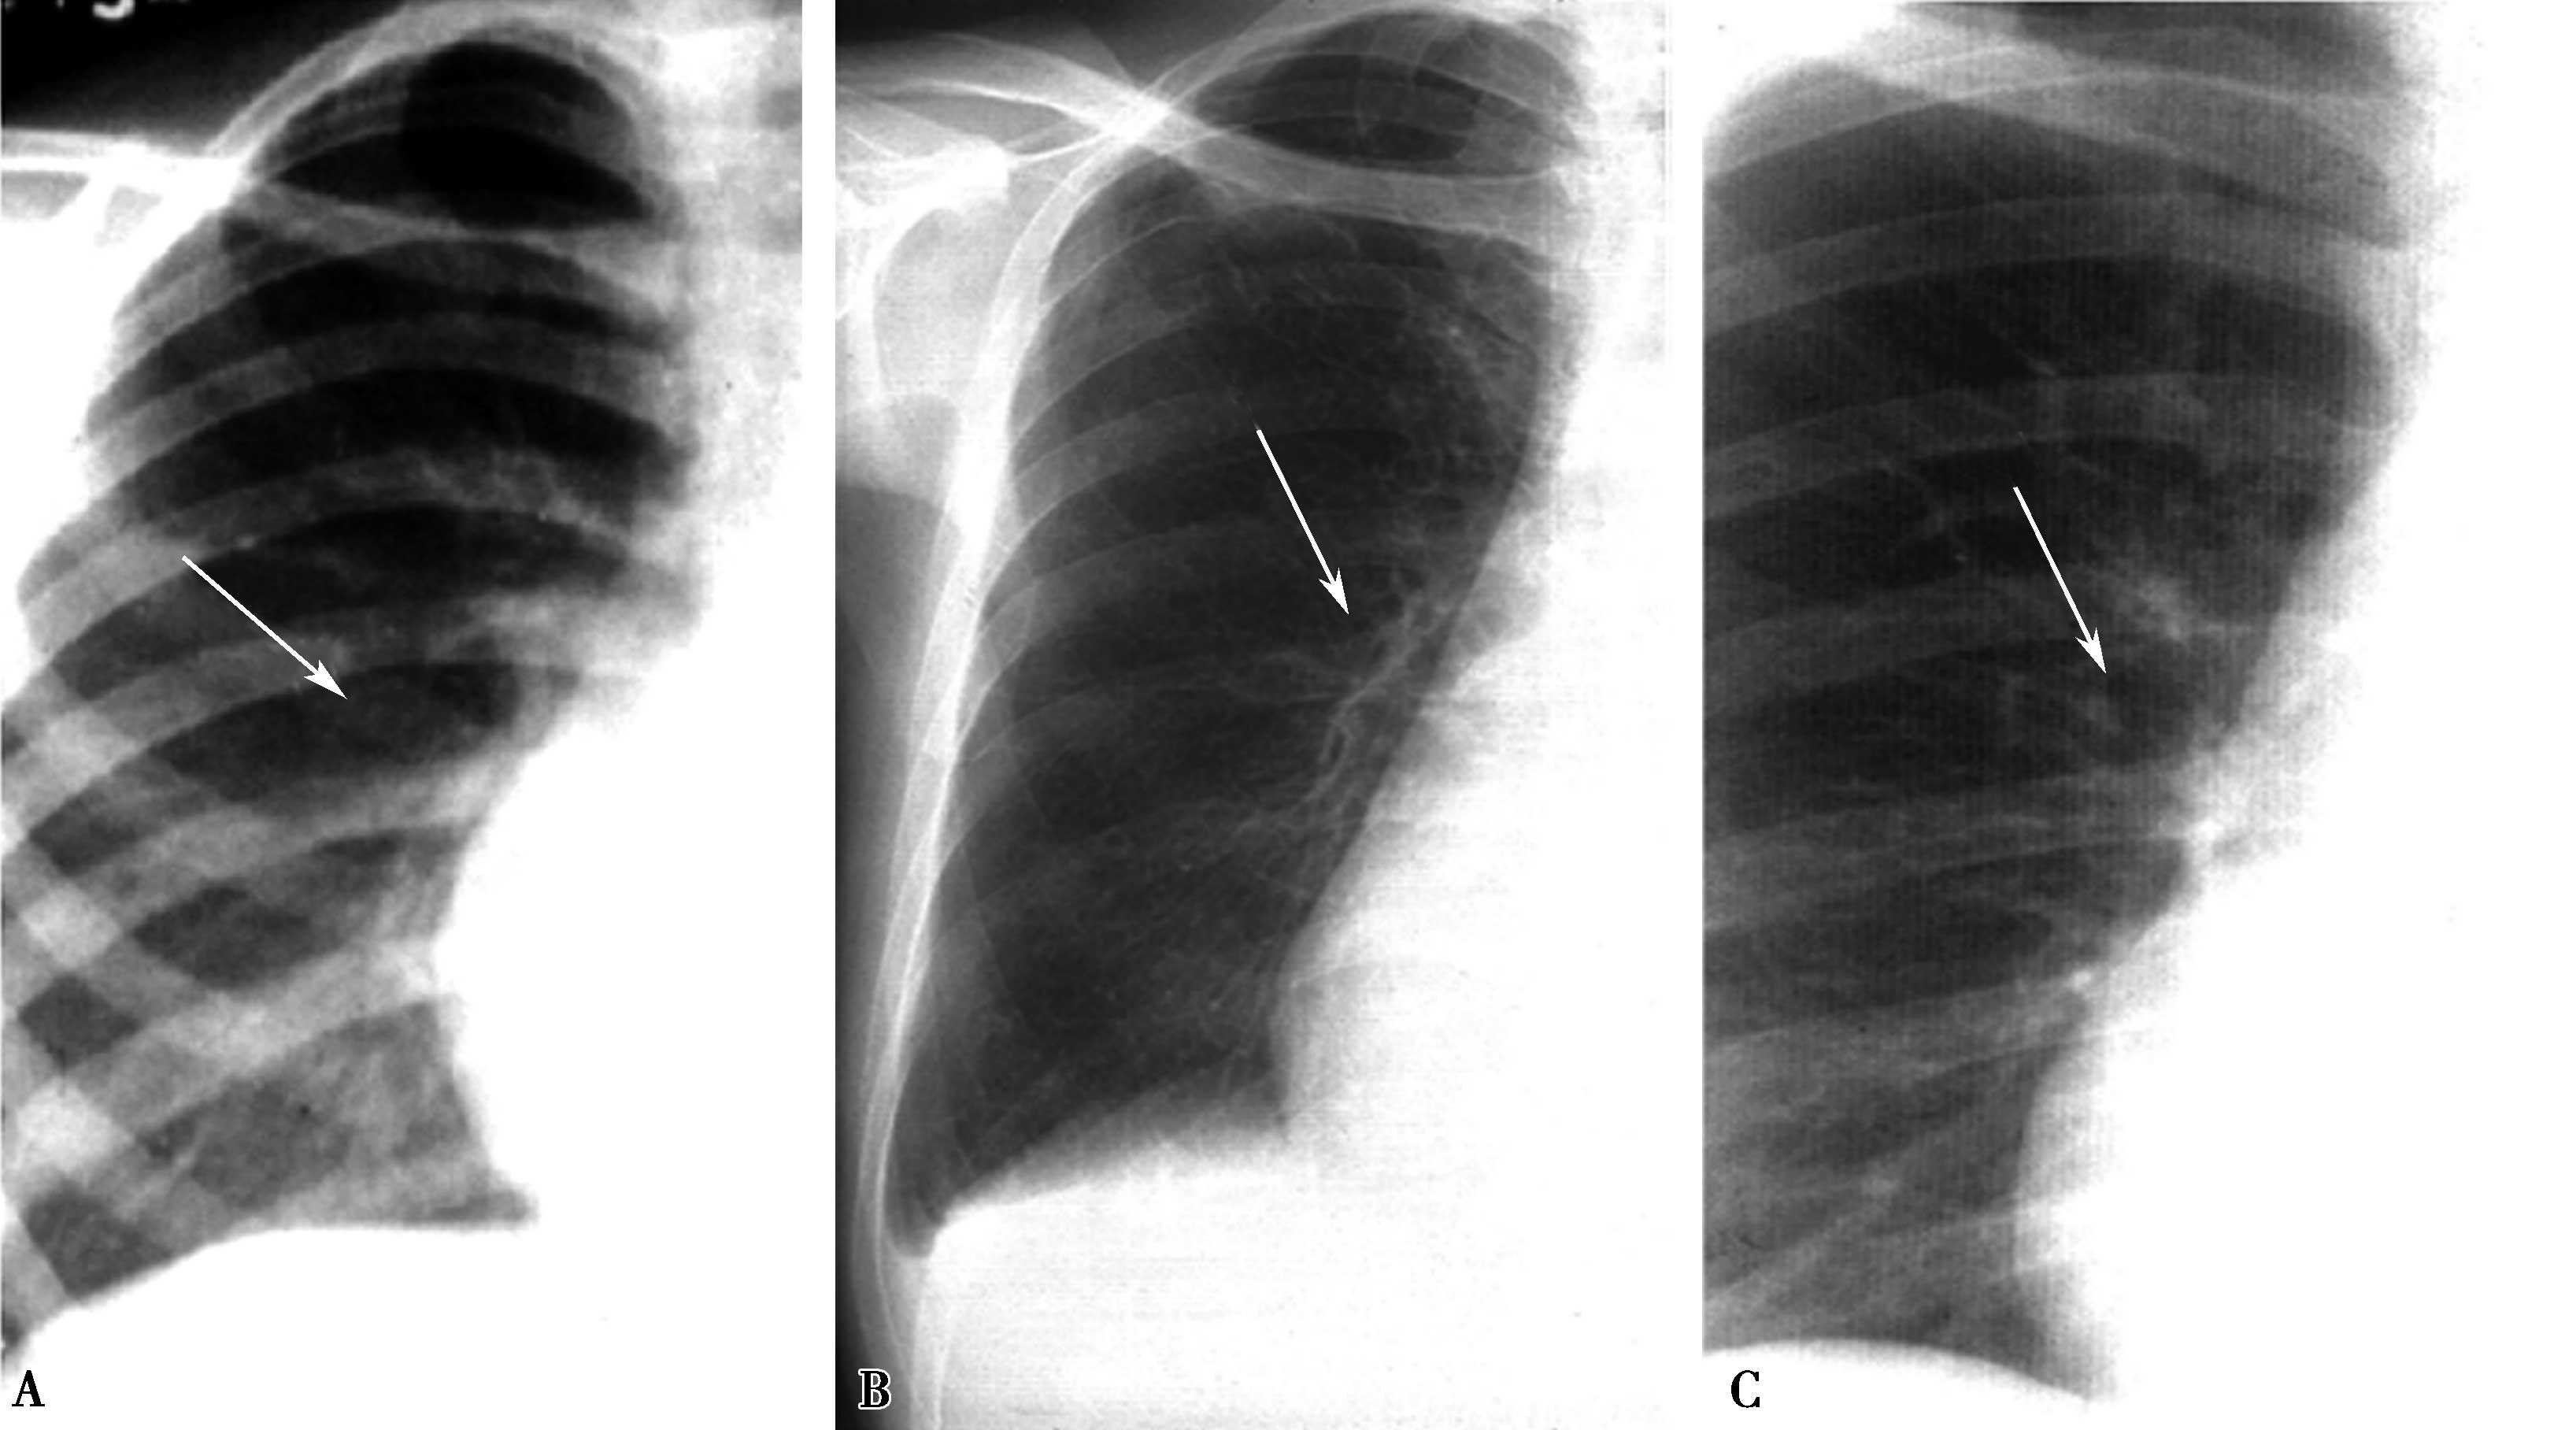

(一)左心房增大(图7-1-2)

1.远达片

左心房耳部膨隆;气管隆突角度开大;左心房高度增大时,可以向心右缘凸出(图7-1-2A↑)。

2.左前斜位

心脏后上缘膨隆,左主支气管抬高(图7-1-2B↑)。

3.右前斜位

心后缘膨隆,服钡食管中段压迹,左心房增大推压食管向后移位(图7-1-2C)。

4.左侧位

心后缘膨隆,服钡食管中段压迹,依左心房增大程度推压食管向后移位。

图7-1-2 左心房增大征象

A.远达片;B.左前斜位;C.右前斜位

(二)左心室增大(图7-1-3)

左心室缘向左膨隆、向下延伸,心尖下垂可达左膈下(图7-1-3A↑)。

心脏后下缘向后膨隆,心后间隙消失,后室间沟下移(图7-1-3B↑)。

3.左侧位

心脏后下缘向后膨隆,心后间隙消失(图7-1-3C↑)。

图7-1-3 左心室增大征象

A.远达片;B.左前斜位;C.左侧位